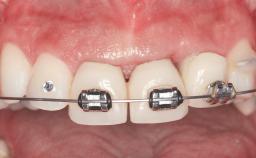

Replacement of Two Central Incisors and One Lateral Incisor with a Fixed Dental Prosthesis on Two Bone-Level Implants

A 38-year-old woman presented with an esthetically unacceptable fixed partial denture replacing teeth 11, 21, 22. She had lost these teeth due to trauma when she was a child. The patient was not in pain but very concerned based on her previous experience that dental treatments had never satisfied her esthetic expectations. She was in good general health and reported no regular medications. No periodontal disease was noted despite the fact that the buccal flange of the prosthesis impeded cleaning of the tooth abutments. The patient did not smoke and complied with home maintenance requirements, as evidenced by her good oral hygiene status.